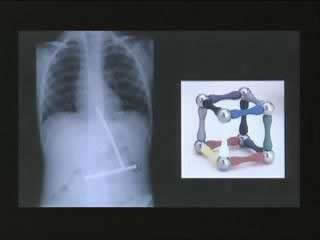

5,磁鐵碎塊——身份不明的美國男孩

X光片顯示,這個男孩一次吞下了一塊磁鐵分成的幾個碎片,而當它們進入小男孩的胃里後,這些磁鐵碎片又相互吸引,吸附在了一起。 ”。